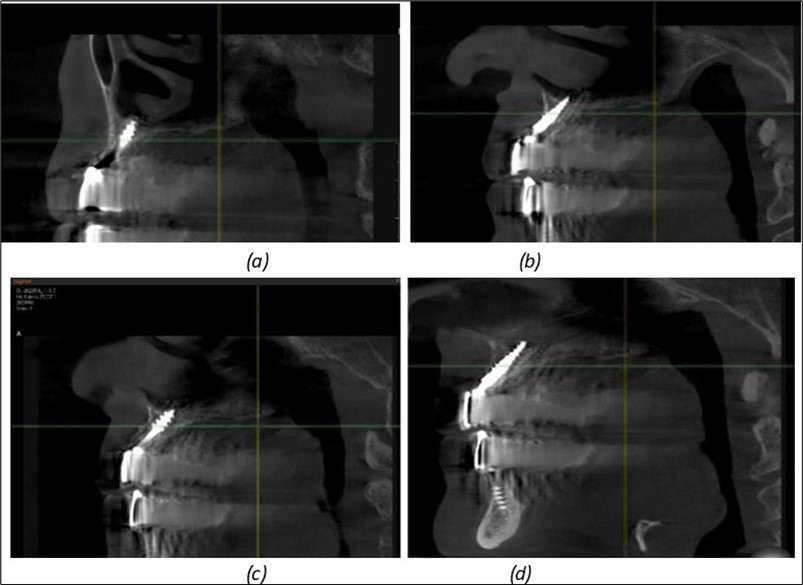

A total of 11 implants is placed in the maxilla, including compressive TPG implants with a polished surface in the maxillary-sphenoid fusion area (Figure 3, Figure 9). Similarly, in the anterior region, final fixation is achieved in the nasal cortex, and BCS corticobasal implants are added in areas with massive bone loss in the frontal region (Figure 3, Figure 8, Figure 11). Additionally, in the palatal sinus cortical area, with the aim of avoiding the addition and sinus lift zone where the second cortical bone no longer exists, 3 implants are placed, 2 in quadrant 1 and 1 in quadrant 2 (Figure 3, Figure 8). Through the Caldwell-Luc sinus lift procedure, the sinus cortical bone is displaced to allow the placement of the graft material and elevation of the sinus membrane. This sinus cortical is no longer recreated at the junction of the graft material and mucosa-sinus membrane, making it impossible to place a corticobasal implant, which relies on the second cortical bone. In the distal mandibular area, after the removal of two stage implants due to massive destruction in quadrant 3, implant placement distal to the mylohyoid line is not possible, as in quadrant 4 (Figure 10). A re-intervention occurs after 5 months to stabilize the area (Figure 12, Figure 14). Also, at the moment of fixation, the tip of one implant fractures, and the decision is made to leave it in place due to regional bone destruction, in order to avoid enlarging the bone defect.

Figure 9.Implants in the pterygoid plateau area: (a) TPG implant fixed in the maxillary-sphenoid junction area, quadrant 1; (b) TPG implant fixed in the maxillary-sphenoid junction area, quadrant 2.

Figure 10.Implants in the palatal sinus cortical area to avoid bone grafting: (a) BCS implant partially fixed in the graft material mass, partially in the palatal cortex; (b) Implant fixed in the palatal cortex at the junction with the nasal cortex, behind the graft material mass.

Figure 11.Implants in the anterior area anchored in the nasal cortex (BCS and TPG): (a), (c) – BCS implants fixed in the nasal cortex; (b), (d) – TPG implants fixed in the second nasal cortex with compression in the trabecular area.

Figure 12.Implants fixed distally in quadrant 4 with fixation at the level of the mylohyoid line: (a) The most distal implant fixed in unaffected bone from the previous restoration; (b) The implant fixed in the area where the two stage implant was removed.